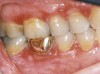

Lichen planus is the mucocutaneous disorder seen most often in the oral cavity (Figure 1). It is a condition of un­known etiology, although a strong autoimmune component plays a role in lesion formation. The disorder usually develops between the ages of 40 and 70 years, and women are affected more often than men.4 Chainani-Wu et al5 reported a male-to-female ratio of 1:2 in 209 patients, while data from the Stomatology Center at Baylor College of Dentistry suggest a 3:1 female-to-male ratio in greater than 800 patients.6

Figure 1  Reticular form of OLP.

Figure 1